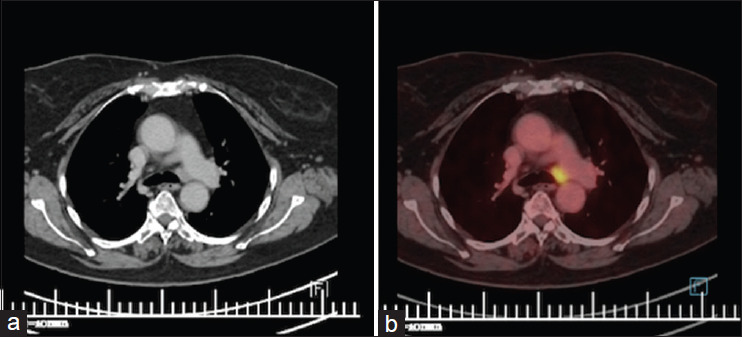

结节病是一种病因不明的复杂多系统疾病,表现为多种症状,常累及多个器官。声带麻痹是罕见的报告与结节病。由于纵隔淋巴结病压迫喉返神经而出现声带麻痹的病例报道很少。我们在此报告了3例因结节病引起的纵隔淋巴结肿大压迫喉返神经而导致声带麻痹的病例,并回顾了相关文献。

Sarcoidosis, is a complex multisystemic disease of unknown aetiology, which manifests via a variety of symptoms frequently affecting multiple organs. Vocal cord paralysis is rarely reported with Sarcoidosis. There have been very few case report of patients presenting with vocal cord palsy due to mediastinal lymphadenopathy causing compression of recurrent laryngeal nerve. We hereby report a case series of 3 patients presenting with vocal cord palsy due to recurrent laryngeal nerve compression by enlarged mediastinal lymph nodes due to Sarcoidosis and also reviewed the supporting literature.